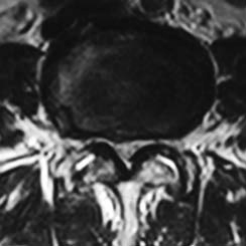

IMAGING STUDIES

Has imaging studies showed grade 1 degenerative spondylolisthesis L45 with moderately severe subarticular and subarticular stenosis at L5S1 and L34.